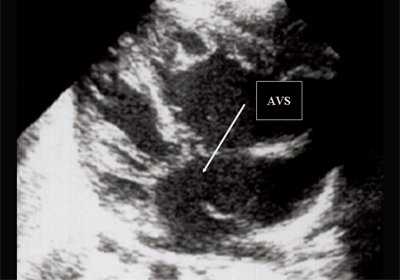

Антенатально при равных величинах давления в желудочках сердца и в предсердиях объемной перегрузки не возникает. В связи с этим ни один из эхокардиографических гемодинамических признаков, используемых у детей и взрослых, не выявляется у плода. К эхокардиографическим проявлениям порока антенатально относится только прямой признак - перерыв ультразвукового луча в области дефекта. Размеры сердца, соотношение размеров желудочков сердца не отличаются от нормы (рис. 5).

Рис. 5. Четырехкамерное сечение сердца плода. Стрелкой указан первичный дефект межпредсердной перегородки (АVS).

В равной степени это относится к дефекту межжелудочковой перегородки (рис. 6), простой форме транспозиции магистральных сосудов (рис. 7, 8), транспозиции магистральных сосудов с дефектом межжелудочковой перегородки (синдром Тауссиг - Бинга) (рис. 9), общему желудочку (рис. 10), общему артериальному стволу (рис. 10), двойному отхождению сосудов от одного из желудочков сердца (рис. 11).

Рис. 6. Дефект межжелудочковой перегородки. Длинная ось сердца. Стрелками показан дефект межжелудочковой перегородки.